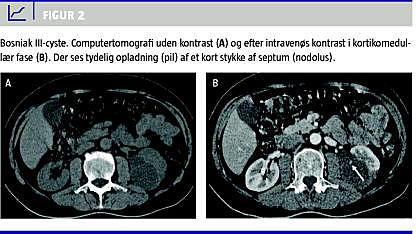

Kategori III

CT-forandringerne (Figur 2 ) i denne kategori kan ikke med sikkerhed afgøre, om læsionen er benign eller malign, hvorfor disse altid bør tilbydes invasiv diagnostik/kirurgisk intervention.